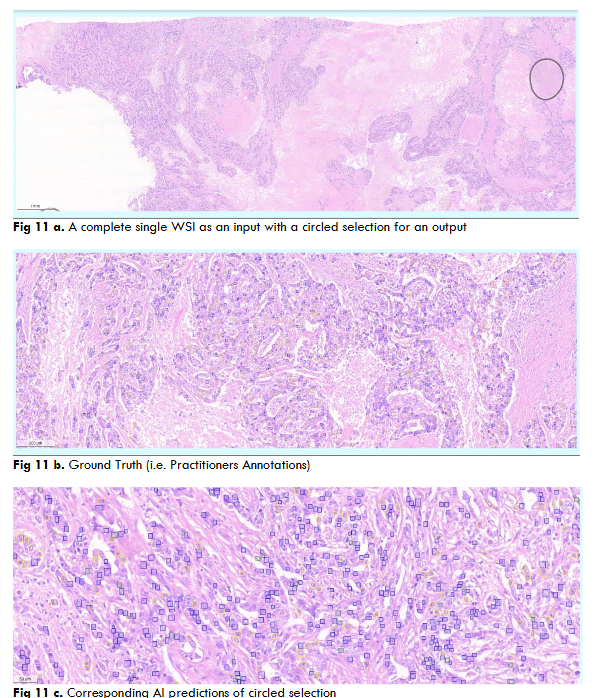

Fig.13 Illustrates resultant output of Breast Cancer Mitosis object segmentation using DC dataset through YoloV5 model. These outputs are individual tiles wise mitosis object segmentation of a single WSI image. Each output contains a. Original inputted image b. Ground Truth, i.e. Practitioners Annotations and c. Corresponding AI predictions.